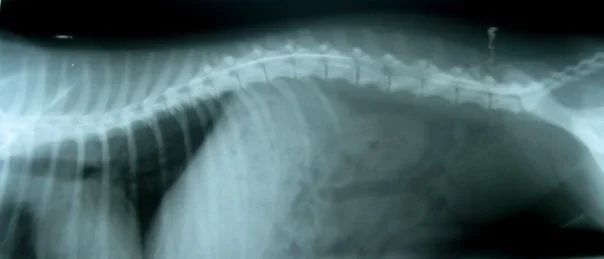

Galería de casos clínicos

Casos clínicos de cirugía (tejidos blandos, traumatología, neurocirugía, artroscopia)